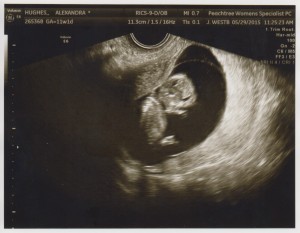

I have some great news! I am preggers. Pregnant. Expecting. Knocked up. It’s traditional to wait until the end of the first trimester to tell everyone, but I’m impatient, so you guys get to find out now (at 11 weeks). Yep, you can totally wish me mazel tov. (I’ll wait  )

This is our first offspring, and he/she was a very welcome surprise. Sam and I are both happy and nervous and Every. Possible. Emotion. On Earth. Because kid! I’m due in December, and poor kid may end up with a Christmas birthday. We’ve already laid down the law to relatives: no joint presents. No really. We may end up celebrating the half-birthdays in July, just to be fair.

See? Pictures!

Isn’t Pip cute? I’m probably hopelessly biased.

But that’s okay  you can totally lie to me and tell me he/she is the most adorable thing ever. (He/she is currently the size of a lime, and a very adorable lime at that.)